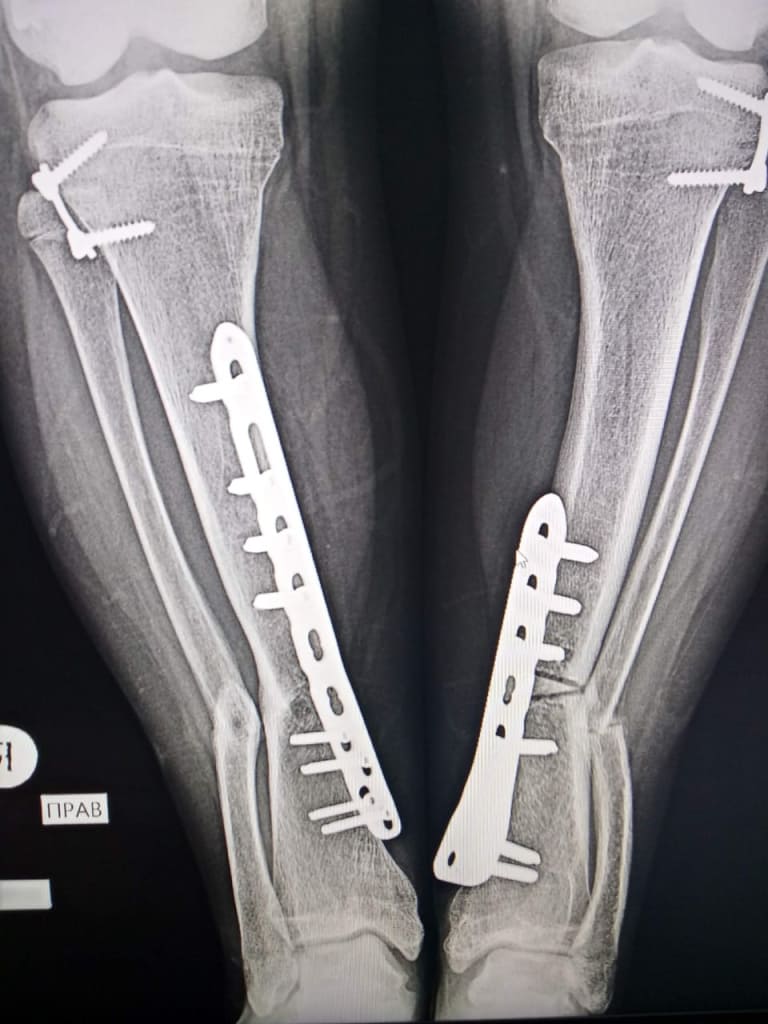

В два года мальчика повезли на консультацию в Москву. Ортопеды сказали: «Фиксируйте ноги, они выровняются!» Целый год ребенку надевали на ноги туторы, но исправить деформацию не получилось. В семь лет Сергею сделали шесть операций, это частично помогло выправить кости и суставы. Маму предупредили: «Пусть сын подрастёт, а там посмотрим».

В 15 лет родители повезли сына в Амурскую областную больницу. Вновь потребовалось исправлять деформацию ног, и юноше сделали еще три операции с двойными переломами и установкой аппарата Илизарова, в котором нужно было лежать долгие недели. Из-за операций и тяжелого периода восстановления Сергей пропустил половину десятого класса. Наверстать занятия было непросто, но в этом помогала цель — поступить в медицинский колледж.

Когда Софья пошла в первый класс, деформация ног у нее значительно усилилась. Больше ждать было нельзя. В июне 2017 года Софье сделали операцию в зоне роста коленных суставов, в ходе которой в кости поставили пластины, чтобы дальше ноги развивались без деформаций. Такой метод называется гемиэпифизиодезом.

Мера оказалась успешной — ноги в районе коленей выровнялись. Однако спустя два года усилилась деформация голеностопных суставов. В июне и ноябре 2019 года девочке провели еще две операции. Но через несколько месяцев в правой голени начали регулярно появляться гнойные свищи. Чтобы убрать очаг инфекции, пластины потребовалось досрочно удалить.

В 13 лет у Софьи на фоне гормональной перестройки остановился рост на 140 см. По мнению ее лечащего хирурга Михаила Петрова, при этих условиях новая малоинвазивная операция не принесла бы ожидаемого эффекта, поэтому девочке провели тяжелую операцию с переломами и без гипсования. Об этом она узнала только, когда отошла от наркоза.

«Она проснулась, отодвинула одеяло, пытаясь понять, почему одна нога двигается, а другая нет. Тут мне и пришлось ей объяснить, что через шесть месяцев предстоит сделать такую же операцию на второй ноге», — рассказывает Сергей. Всего Софья перенесла уже несколько операций, но удлинить и выправить ее ноги полностью врачам не удалось. Отец с этим не спешит, говорит: повзрослеет — сама примет решение.